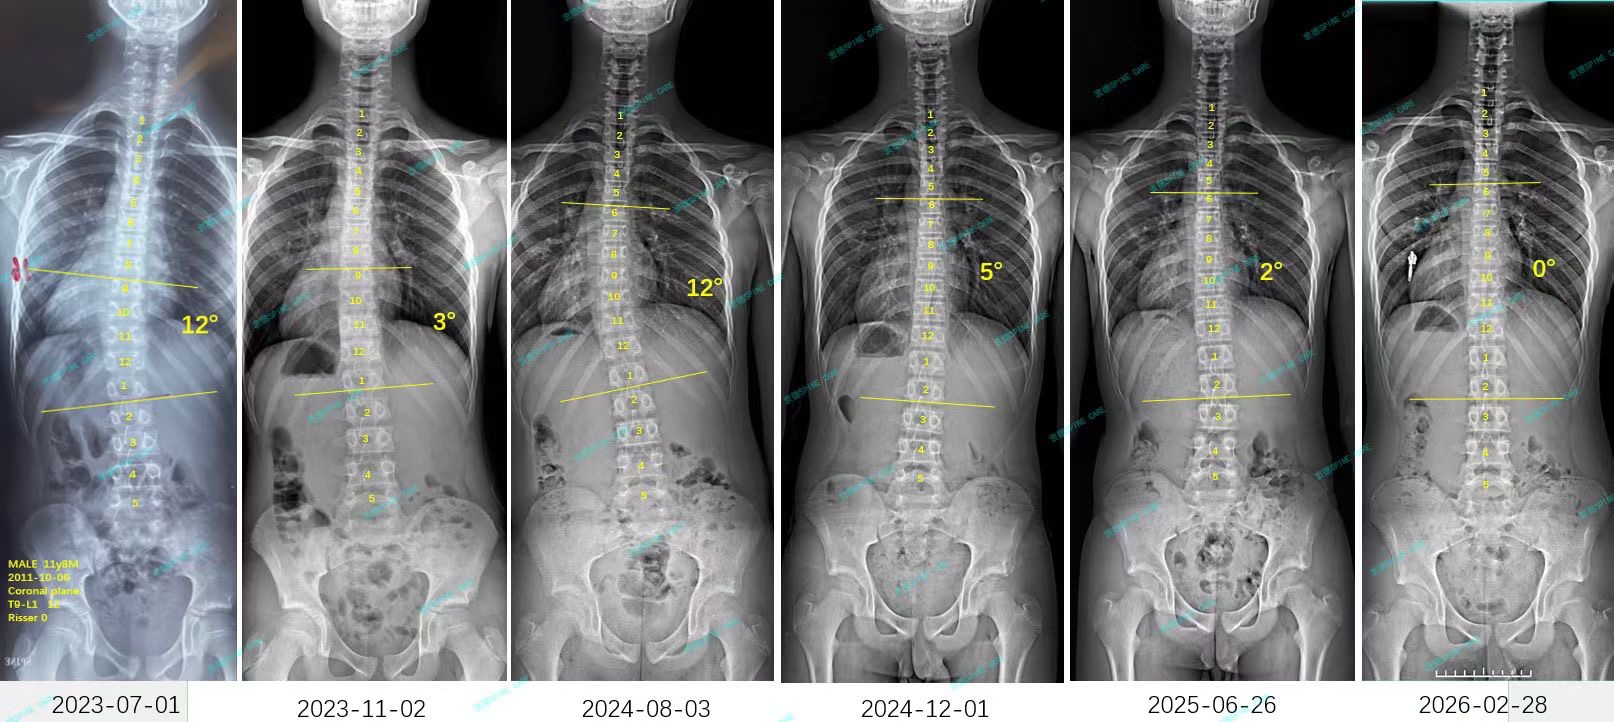

衷德脊柱,我们只关注侧弯保守治疗~

Zhongde Spine, bending no breaking ~